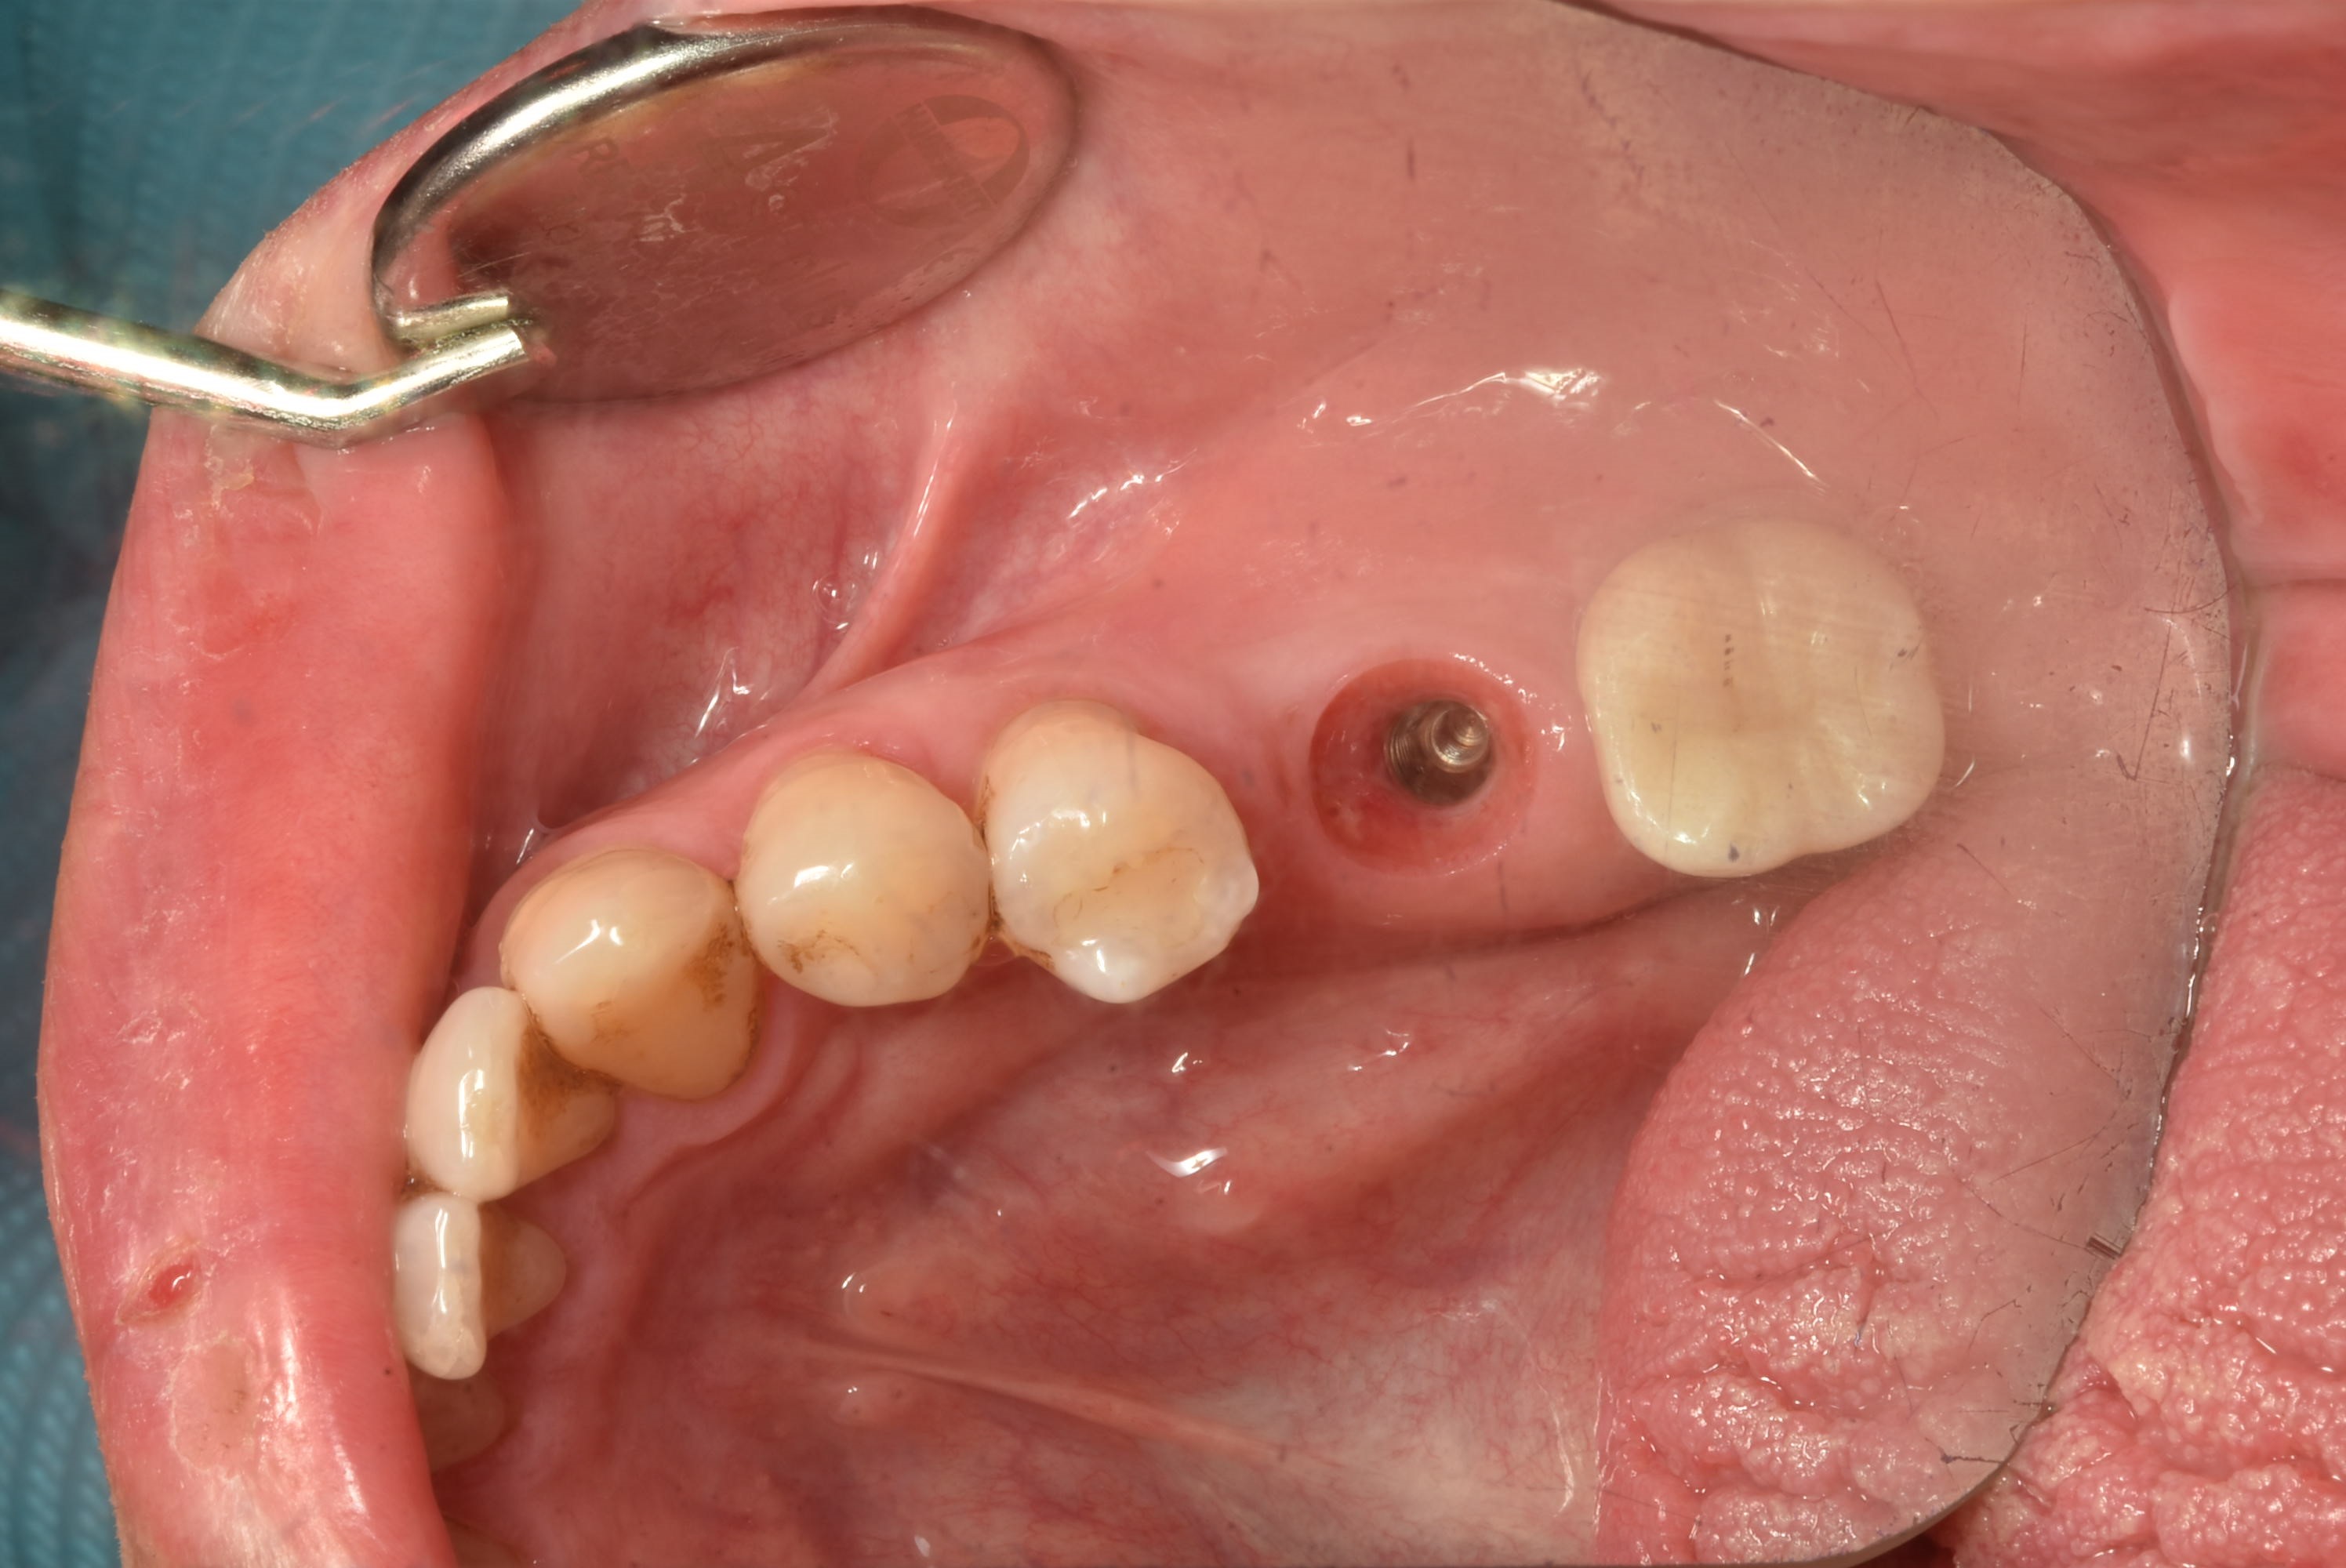

案例三

立即拔除牙根不好的牙齒

立即植入植體

鎖上癒合螺帽

2-3個月癒合,7-10天完成假牙 ,試戴、調整咬合高度並鎖上,封填,完成